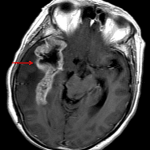

- Hypoattenuating lesion centered in the right frontal/anterior temporal lobe with extensive surrounding vasogenic edema

- Associated 10 mm right to left midline shift, right uncal herniation, and partial effacement of the right lateral ventricle

- Enlargement of the left lateral ventricle, particularly the temporal horn

- Brain tumor, herniation, ventricular entrapment

Hypoattenuating lesion centered in the right frontal/anterior temporal lobe with extensive surrounding vasogenic edema. The primary differential considerations are brain tumor (primary or metastatic) and brain abscess. Recommend brain MRI with and without contrast for further evaluation.

Associated 10 mm right to left midline shift, right uncal herniation, and partial effacement of the right lateral ventricle. No cerebellar tonsillar herniation. Entrapment of the left lateral ventricle with developing obstructive hydrocephalus.